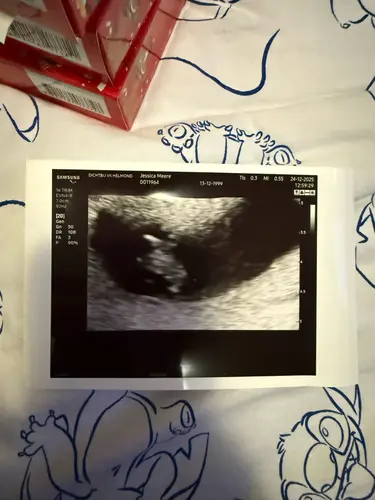

Afgelopen maandag ongeveer 8 weken ❤️ van kruin tot stuit 1,6cm